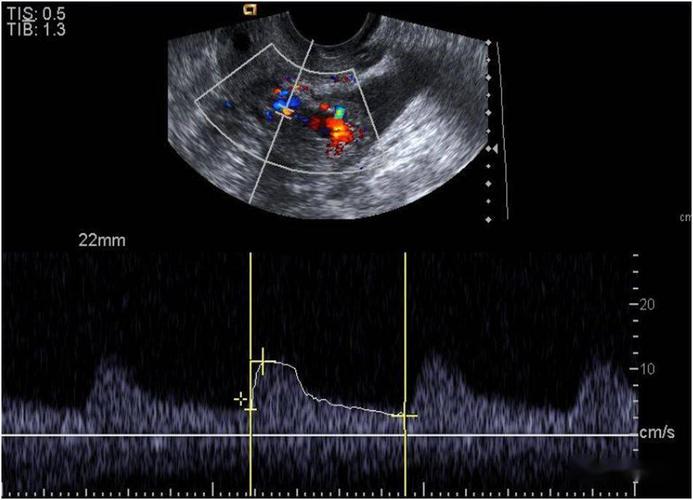

子宫穿孔的超声诊断

超声典型病例子宫穿孔

子宫穿孔彩超下表现

子宫穿孔超声表现图